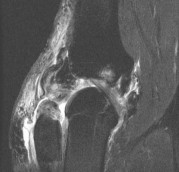

A 45-year-old recreational athlete presents with acute medial knee pain after feeling a 'pop' while deep squatting. MRI demonstrates an extrusion of the medial meniscus of 4 mm and a complete radial tear at the posterior root. Which of the following best describes the primary biomechanical consequence of this specific injury pattern?

Correct Answer: Loss of hoop stresses leading to peak contact pressures equivalent to a total meniscectomy

Explanation:

A posterior medial meniscus root tear disrupts the circumferential hoop stresses that the intact meniscus relies on to dissipate axial loads. Biomechanical studies demonstrate that a posterior root tear is functionally equivalent to a total meniscectomy in terms of decreasing contact area and dramatically increasing peak tibiofemoral contact pressures, leading to rapid chondrolysis and osteoarthritis if left untreated.